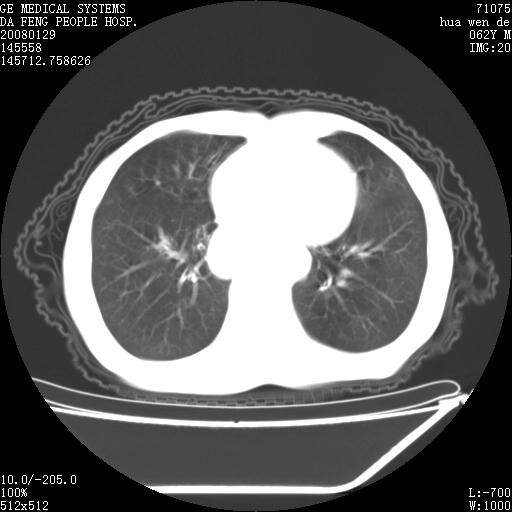

男性,67岁。作肺部检查时发现

理由:1、右上肺内病灶,空洞形成,有液平。

2、肺内多处炎症。

3、前段肺内炎症,支气管引流通畅,与肿块无关系。

1.整个食管扩张,未见明显占位性病变,贲门区亦未见明显占位病变,考虑:贲门失驰缓症;

2.右上肺病变边缘可见毛刺,囊壁厚度不均匀,周围境界较清楚,未见炎性渗出性影,右上肺外带可见片状影,边缘不清,考虑:肺癌伴空洞形成、右上肺炎。

食管全程扩张,壁均匀不厚,喷门失弛缓症

右上肺空洞可见液平,临近肺野磨玻璃密度,考虑1.结核2.脓肿